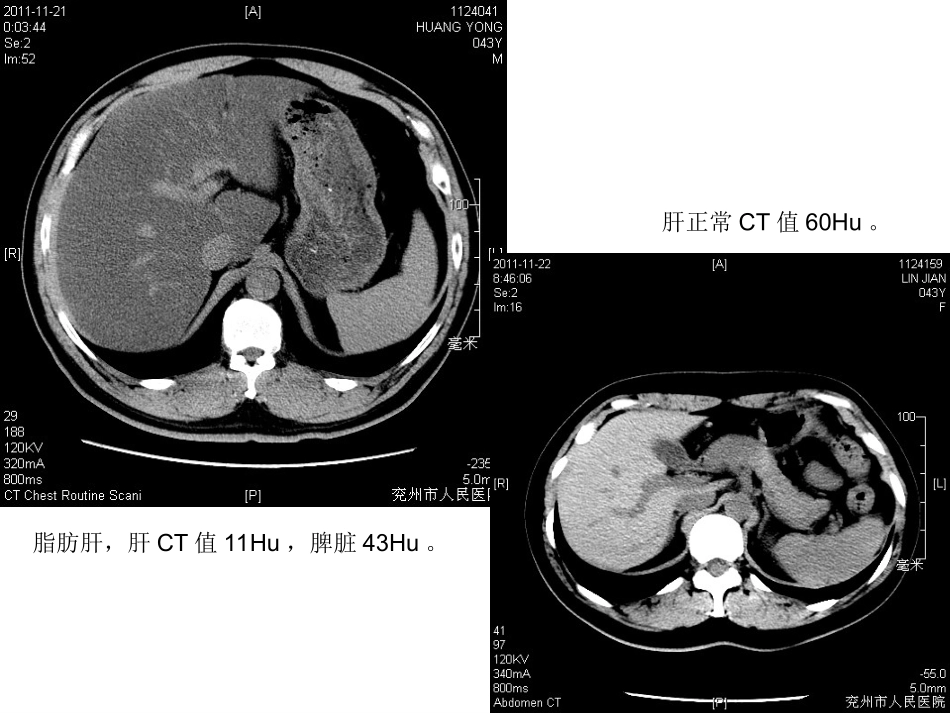

典型病例消化系统脂肪肝,肝CT值11Hu,脾脏43Hu。肝正常CT值60Hu。右肝囊肿右肝囊肿T1T1加权像加权像T2T2加权像加权像T2T2加权像加权像胆囊多发结石胆囊多发结石MRCPMRCPT2T2加权像加权像T2T2加权像加权像•胆囊结石MR:060596肝海绵状血管瘤CT平扫MR平扫MR:060683增强扫描右肝海绵状血管瘤右肝海绵状血管瘤T1T1加权像加权像T2T2加权像加权像T1T1增强像增强像T1T1增强像增强像肝脂肪变性并肝血管瘤MR:060649巨大肝血管瘤MR:060212增强扫描:动脉期、门脉期、延迟扫描左肝癌,门静脉瘤栓左肝癌,门静脉瘤栓T1T1增强像增强像T2T2加权像加权像T2T2加权像加权像十二指肠乳头腺瘤MR:060432腹膜后畸胎瘤IVP腹膜后畸胎瘤胰腺癌MR平扫胰腺癌MR增强泌尿系统右肾挫伤及复查•肾囊肿左肾结石左输尿管结石并肾积水输尿管积水MR:060487肾细胞癌(肾细胞癌(3.23.2厘米)未突破肾包膜厘米)未突破肾包膜RobsonRobsonⅠⅠ期期,,TNMTNMTT22NN00MM00肾细胞癌突破肾包膜,肾细胞癌突破肾包膜,RobsonRobsonⅡⅡ期期,,TNMTNMTT3a3aNN00MM00左肾错构瘤左肾错构瘤T1T1加权像加权像T2T2加权像加权像T2T2加权像加权像神经源性膀胱神经源性膀胱T2T2加权像加权像MRUMRUT1T1加权像加权像输尿管移行细胞癌T2T2加权像加权像MRUMRUT1T1加权像加权像膀胱肿瘤MR:050585•膀胱结石生殖系统双子宫、双阴道MR:050634八月正常胎儿MR:050632胎儿肾脏畸形二、子宫肌瘤•是子宫最常见•的良性肿瘤。•根据位置,•子宫肌瘤分为•浆膜下、壁内•、粘膜下型及•带蒂外生型。子宫肌瘤MR:06111子宫内膜癌并卵巢转移MR:061511•宫颈囊肿男性盆腔前列腺、精囊前列腺显示前列腺增生前列腺增生T2T2加权像加权像•前列腺增生图前列腺癌前列腺癌BB期期前列腺癌前列腺癌CC期期左侧精囊腺出血左侧精囊腺出血T1T1加权脂肪抑制像加权脂肪抑制像T2T2加权脂肪抑制像加权脂肪抑制像•前列腺癌图SagT1WI增强隐睾